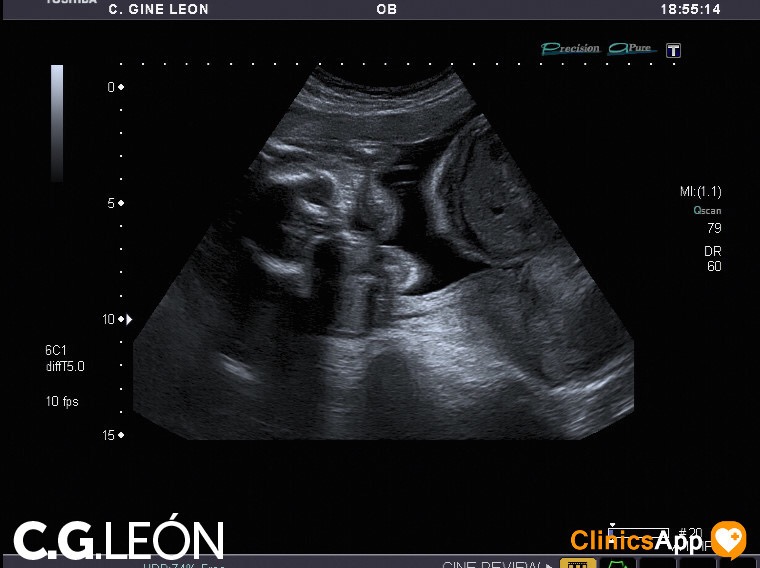

Aquí las fotos de la quinta ecografía, nada que destacar excepto que la ginecóloga estaba de mala leche y no se esmeró demasiado en las fotos. Hay una en la que se ve una mano, en directo se distinguía mejor, claro, porque se vio abierta como en la foto y luego la cerró. Pero por lo general encuentro de difícil interpretación este lote de fotos.